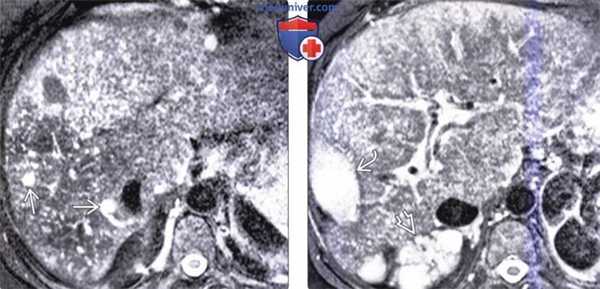

(Слева) На Т1 ВИ GRE opposed-phase МР томограмме определяются множественные кисты печени, обладающие различными сигнальными характеристиками. Некоторые из них гипоинтенсивны, как этого следует ожидать от простых кист с жидкостным содержимым, другие дают промежуточный по интенсивности сигнал. Как минимум в одной из них визуализируется перегородка и неоднородное содержимое, обусловленное «старым» кровоизлиянием.

(Справа) На Т2 ВИ МР томограмме у этого же пациента видна комплексная структура содержимого некоторых кист: неосложненные кисты остаются равномерно гиперинтенсивными, содержимое осложненных кист становится неоднородным.